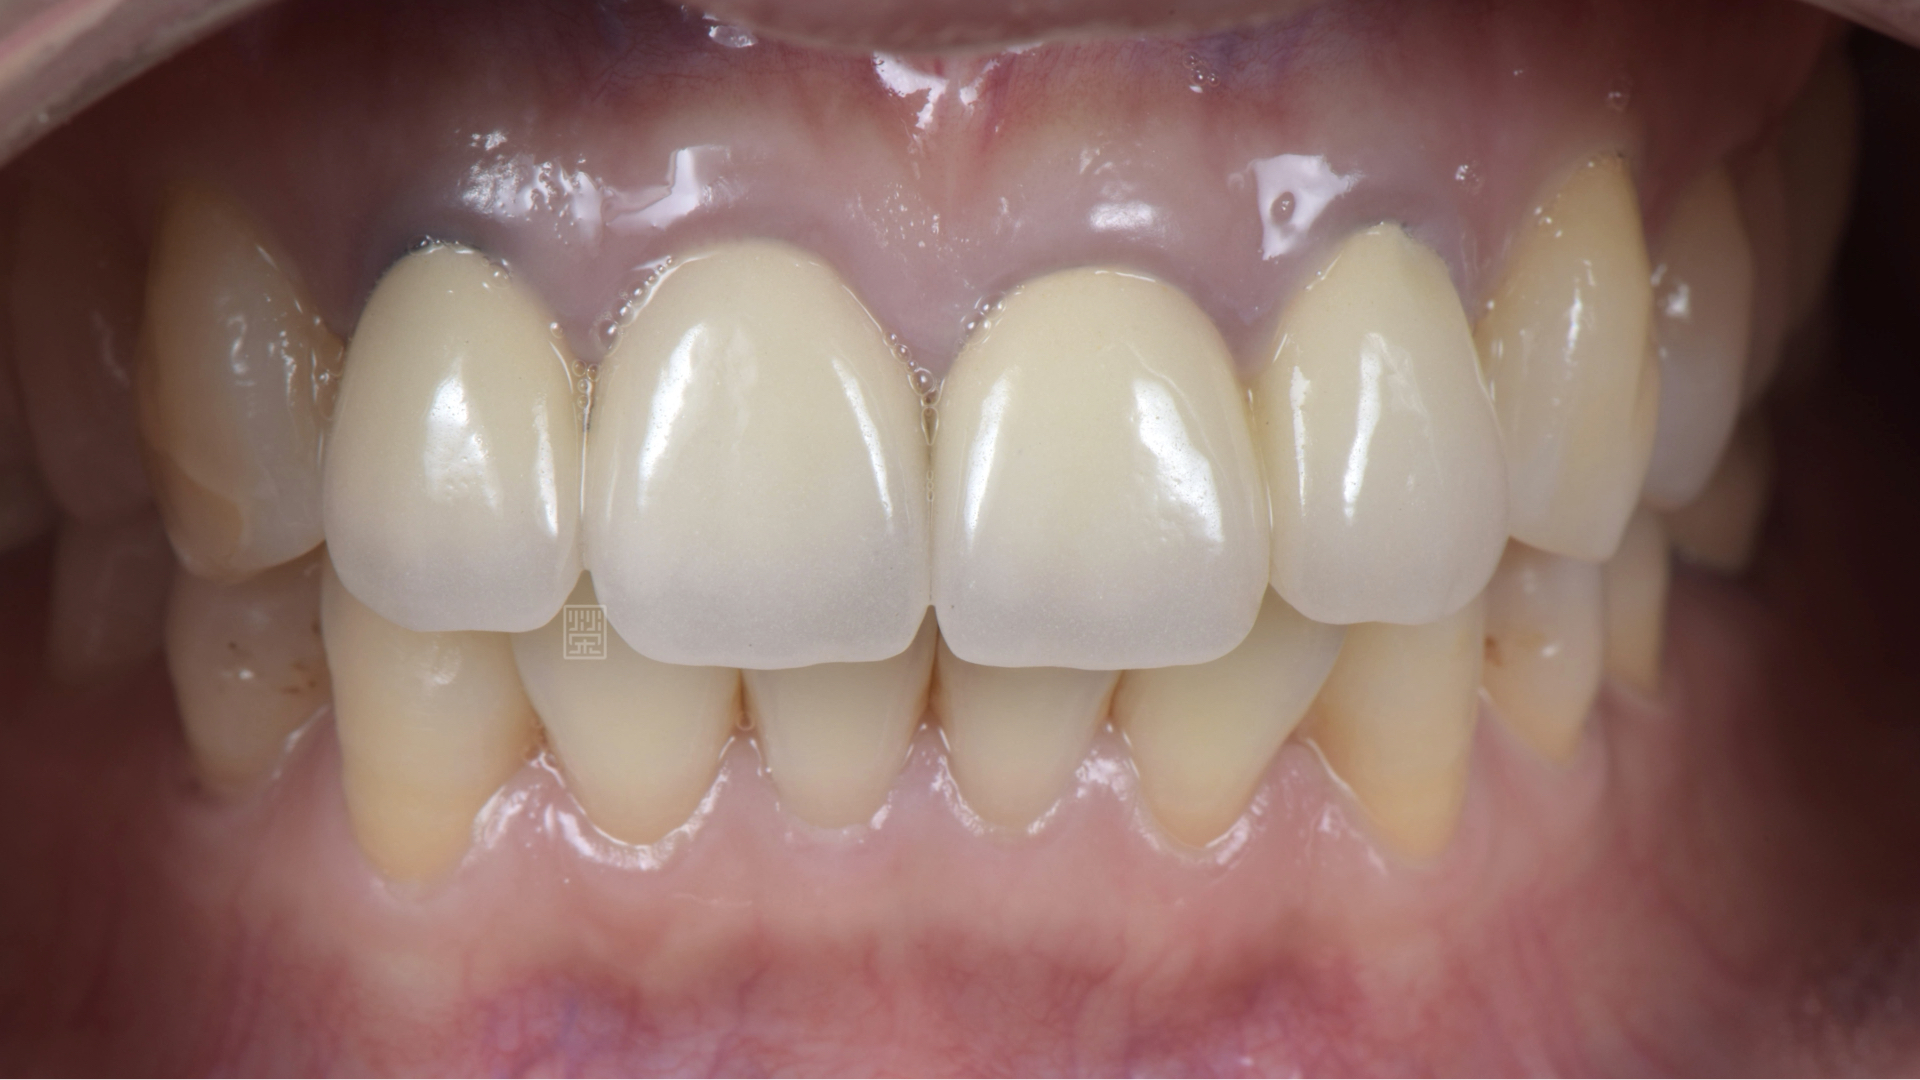

門牙全瓷冠完成

和諧燦爛的笑容